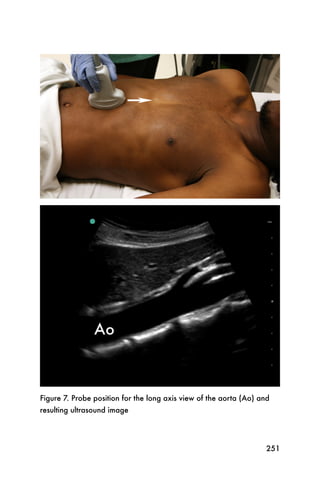

2. Bernardi E, Camporese G, Büller HR, et al. Serial 2-point

ultrasonography plus D-dimer vs whole-leg color-coded Doppler